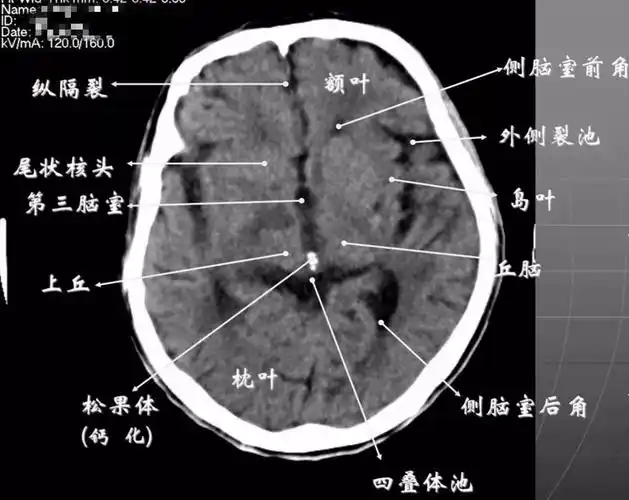

颅脑ct怎么看?正常和异常影像分别是什么?干货满满!